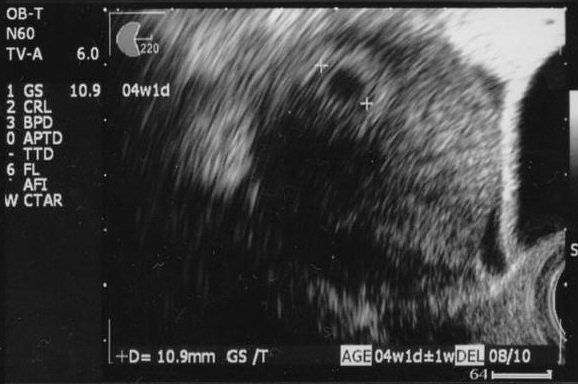

妊娠4週目のエコー写真